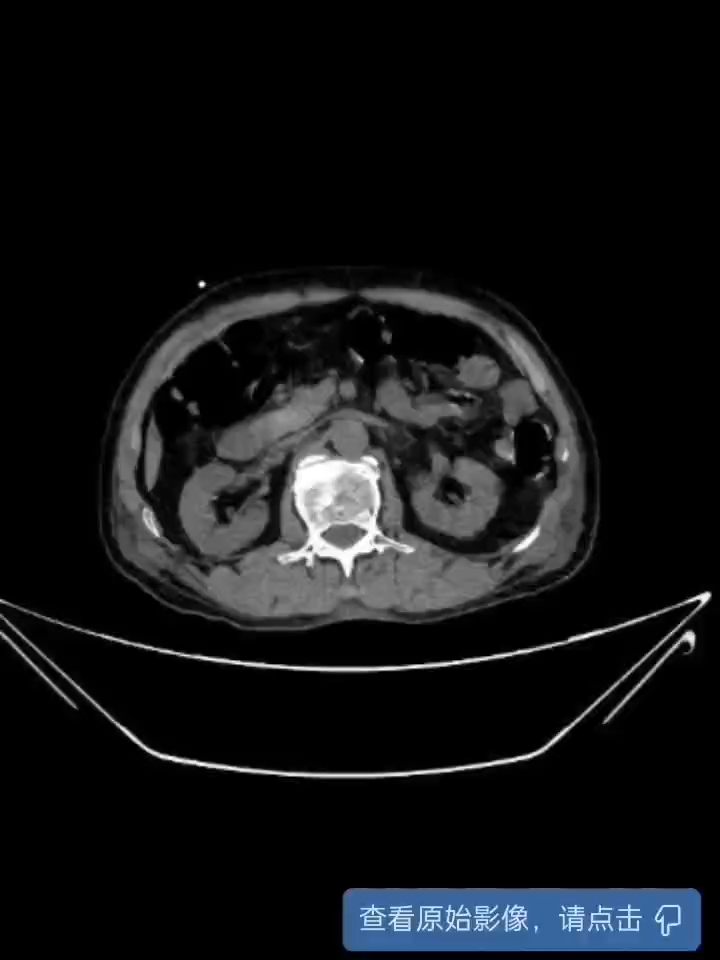

这个手术做的比较狼狈,一开始想给他做剜除,但奈何不好找边界,没有成功,切的过程中还遇到电切环出问题,更换电切环。最后发现还是捅出了篓子,幸好早有所耳闻,腹股沟置管引流出膀胱周围液体,但引出不多,所幸腹腔置管(胆囊周围穿刺点,超声引导下穿刺),引出1000多ml积液。术后安全恢复出院。

对于这种电切后直接出现腹腔积液及膀胱周围积液的,应该就是哪儿切穿了,但总的手术视频没有看出来。最后一个视频没有录制成功,各位大佬将就着看,请多指教。